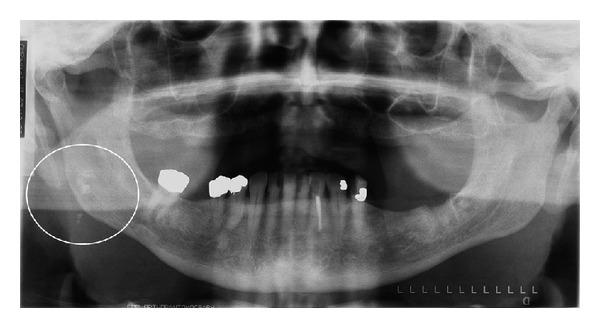

Objective. The purpose of this study was to determine the prevalence of tonsiliths in patients attending the oral and maxillofacial radiology clinic of The University of Iowa and to determine if there is any correlation between the presence of tonsiliths and the presence of stones in other body tissues, ducts, or organs. Study Design. This was a two-part study. The first part was a prevalence study whereas the second was a matched pair case-control study. The matched pair case-control study commenced after the prevalence study was concluded. No new or unusual radiographs were made in this study. The study only reviewed radiographs that were made for clinical purposes. Results. A total of 1524 pantomographs were reviewed and 124 subjects (53 males and 71 females) aged 9 years and 2 months to 87 years (mean age 52.6 years) were included for data analysis. Thirty-eight subjects had single tonsiliths whereas 86 subjects had multiple tonsiliths. The prevalence of tonsiliths in the study population was 8.14%. A total of 20 subjects were included in the second part of the study, comprising 10 each for matched pair case-control groups. The observations did not indicate any correlation between the presence of tonsiliths and the presence of stones in other body tissues, ducts, or organs. Conclusion. The prevalence of tonsiliths in our study population was 8.14%. The observations in our study do not support any correlations between tonsiliths and calcifications in other body tissues, organs, or ducts.

目的。本研究的目的是确定就诊于爱荷华大学口腔颌面放射科诊所的患者中扁桃体结石的患病率,并确定扁桃体结石的存在与其他身体组织、导管或器官中结石的存在之间是否存在任何关联。研究设计。这是一项分为两部分的研究。第一部分是患病率研究,而第二部分是配对病例对照研究。配对病例对照研究在患病率研究结束后开始。本研究未拍摄新的或特殊的X光片。该研究仅回顾了出于临床目的拍摄的X光片。结果。共回顾了1524张全景片,纳入124名年龄在9岁2个月至87岁(平均年龄52.6岁)的受试者(53名男性和71名女性)进行数据分析。38名受试者有单个扁桃体结石,而86名受试者有多个扁桃体结石。研究人群中扁桃体结石的患病率为8.14%。研究的第二部分共纳入20名受试者,配对病例对照组各10名。观察结果未表明扁桃体结石的存在与其他身体组织、导管或器官中结石的存在之间存在任何关联。结论。我们研究人群中扁桃体结石的患病率为8.14%。我们研究中的观察结果不支持扁桃体结石与其他身体组织、器官或导管中的钙化之间存在任何关联。